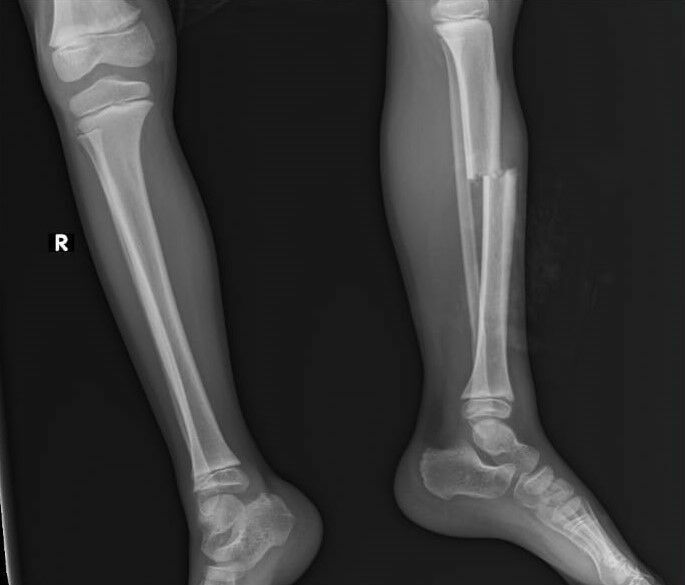

Yaralı olarak Kepez Devlet Hastanesi'ne kaldırılan Eymen, burada tedavi altına alındı. Sol bacağının kaval kemiği kırılan ve çeşitli yerlerinde kesiler bulunan Eymen'in tedavi süreci devam ediyor.